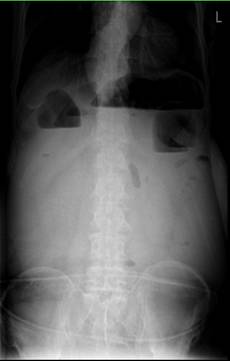

运用小肠减压管为晚期肿瘤患者实施肠梗阻球囊扩张术